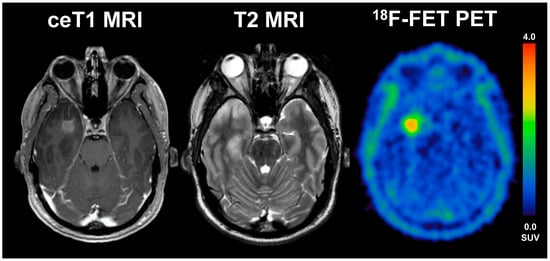

Interestingly, no differences between LTS and STS were observed with regard to the static uptake intensity parameters on PET. Of note, one STS patient was rated 18F-FET-negative with 18F-FET-uptake even lower than the respective background activity, i.e., photopenic glioma. In line with the current literature describing that photopenic tumors could have a high risk for harboring aggressive tumors [23,24,25], the current patient with photopenic, IDHwt glioma on 18F-FET PET presented also with poor OS, subsequently classified as STS. This finding underlines that photopenic gliomas should be managed more actively (see Figure 5).

Figure 5.

56-year old male patient with anaplastic astrocytoma (WHO grade III, IDH wildtype, MGMT unmethylated, TERTp wildtype) and a photopenic aspect on 18F-FET PET. Overall survival was 10 months only (STS) under single therapy with radiotherapy.